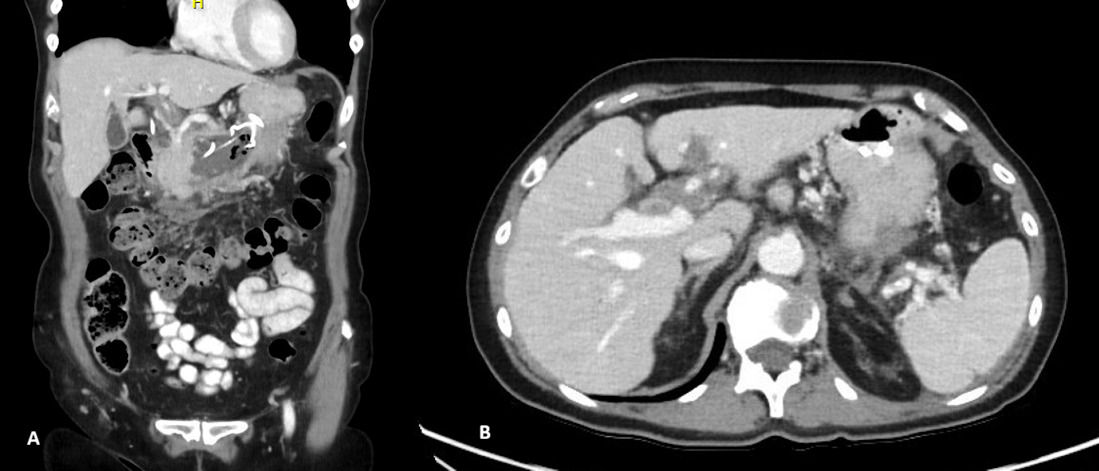

Two weeks later, a repeat CTA demonstrated interval resolution of the previously identified pseudoaneurysms arising from the right, intermediate, and left hepatic arteries. The right and intermediate hepatic arteries were of markedly reduced calibre and tapered shortly after their origins, suggesting proximal arterial occlusion. The absence of contrast opacification within the previously visualised aneurysms was attributed to occlusion of the feeding vessels. Peripancreatic inflammatory stranding had mildly improved, and the previously noted lesser sac collection was no longer visualised (Figure 4).

Final follow-up CT imaging, performed 4.5 months after initial presentation, demonstrated only mild irregularity of the left hepatic artery with a small 2 mm fusiform dilatation. There was minimal residual irregularity along the inferior aspect of the common hepatic artery and a small, thick-walled residual fluid collection measuring approximately 1 cm located between the pancreatic neck and stomach. No new vascular abnormalities were identified (figure 5).